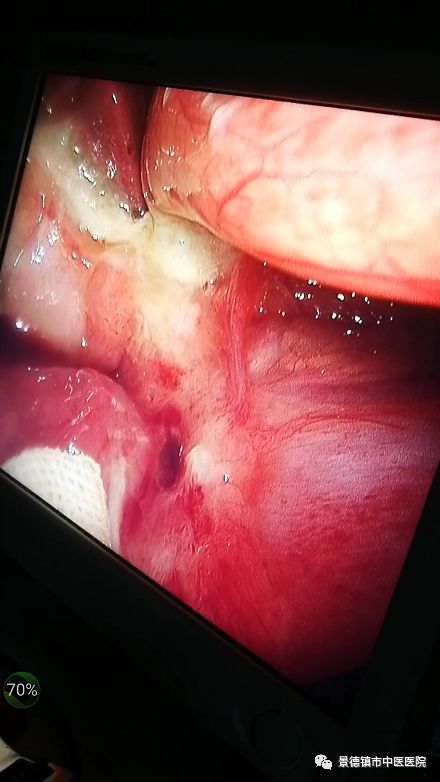

“哎呀!疼,疼,醫(yī)生,醫(yī)生!”五十分鐘后,一陣陣的呻吟聲飄蕩在晚上安靜的走廊里。醫(yī)生們馬上接診病人到病房進(jìn)行進(jìn)一步的檢查,經(jīng)過問診,查體,抽血化驗(yàn)等一系列的檢查,為了盡快減輕甚至解除患者的病痛,本著醫(yī)者仁心的醫(yī)務(wù)人員(無論是病房還是輔助科室),都相當(dāng)配合,最終快速及時(shí)確診是胃穿孔,需立即手術(shù)。否則病情會進(jìn)一步加重。經(jīng)家屬同意后,醫(yī)生護(hù)士立即做術(shù)前準(zhǔn)備,醫(yī)生們討論完病情及手術(shù)方式。20:40我們手術(shù)室快速地準(zhǔn)備手術(shù)相關(guān)用物,通知人員到位,大家沒有受天氣的原因影響,都及時(shí)到位。21:00手術(shù)順利開展。病人的病情如下圖。

大家都聚精會神的做手術(shù),我們張?jiān)洪L也親臨指揮。看下圖: